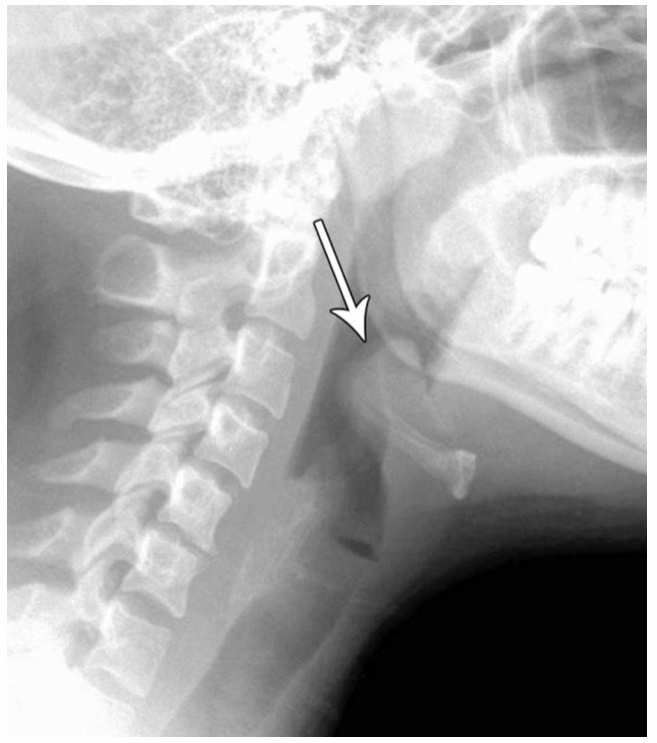

STEEPLE SIGN ON X-RAY

CROUP

THIS X-RAY IS A SIGN OF WHAT IN PEDIATRICS?